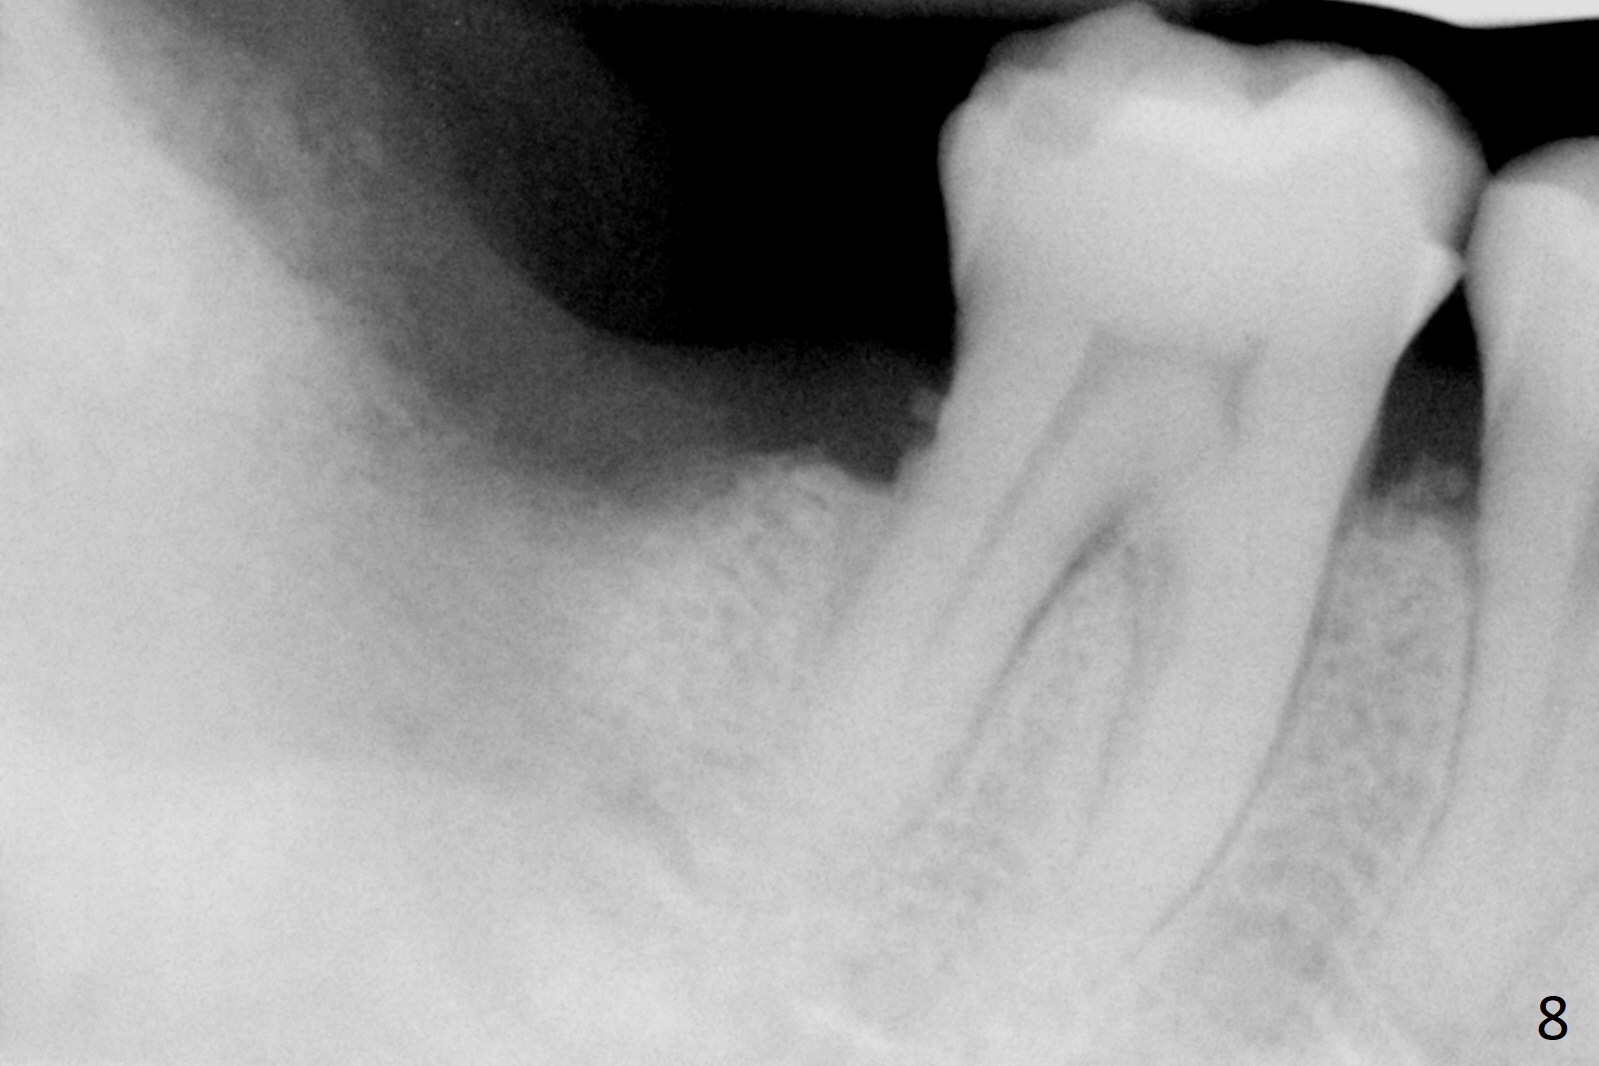

A 50-year-old man, a smoker, presents to clinic with pain of the tooth #15 with apparently occlusal trauma (Fig.1). Two years and three months after #15 extraction, he returns for #31 extraction (Fig.2) and socket preservation (Fig.3). The socket depth is 17 mm along the long axis of the socket 2.5 months post extraction (Fig.4, gingival level). Initial osteotomy is created in the mesial slope of the socket for 14 mm (Fig.5). After sequential osteotomy, a 6x17 mm tap is seated shallower (Fig.6) than the 2 mm drill (Fig.5). Following further osteotomy, a 7x14 mm implant is seated incompletely (Fig.7), which was not found intraop. The implant becomes loose with purulent discharge 19 days postop. The patient returns for 2nd placement 2 months post implant removal (Fig.8). Osteotomy is created probably in the mesial slope with 17 mm (bone level, Fig.9). After insertion of 5 (Fig.10) and 6 (Fig.11) x20 mm taps (tissue level), a 6x20 mm tissue-level implant is placed with clearance from the Inferior Alveolar Canal (Fig.12 yellow dashed line). The implant is restored 8.5 months postop (Fig.13) without bonding 5 mm 0 degree unipost. The crown dislodges 4 months post permanent cementation. Still the patient complains of small crown without occlusal contact. Impression is taken for a new normal-sized crown. The new crown becomes loose 1 year 9 months post cementation (Fig.14). The teeth #14 and 15 remain unrestored.